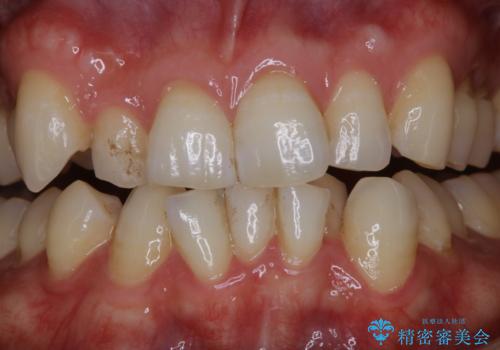

1日で着色を除去し綺麗な歯に

- 前歯の汚れが気になるため、綺麗にしたいとのことで来院されました。PMTC30分コースを行いました。

毎日丁寧に歯磨きをしていても、日常生活での飲食物などにより着色してしまうことはあります。PMTCでは、歯の表面の凸凹にミネラルを補給して、ツルツルの表面に仕上げます。定期的にPMTCを行うことにより、歯質の強化になり着色がつきにくい状態になります。